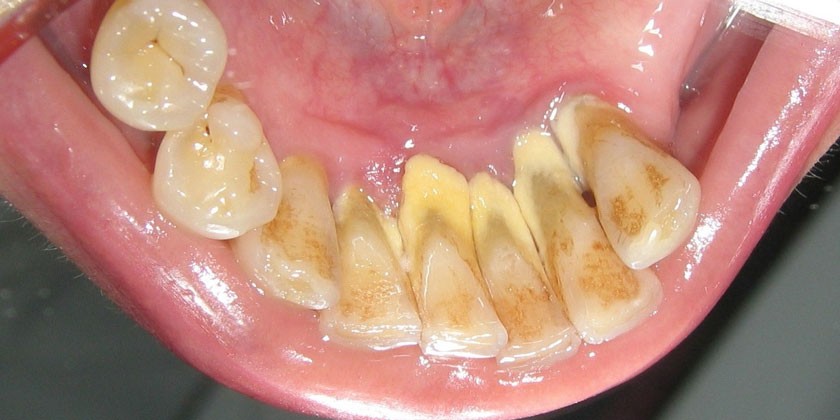

- зубной налет или зубной камень;

- скопления мягкого микробного налета на зубах;

- зубной камень.

- мягкий зубной налет;

- твердые отложения на поверхности зубов;